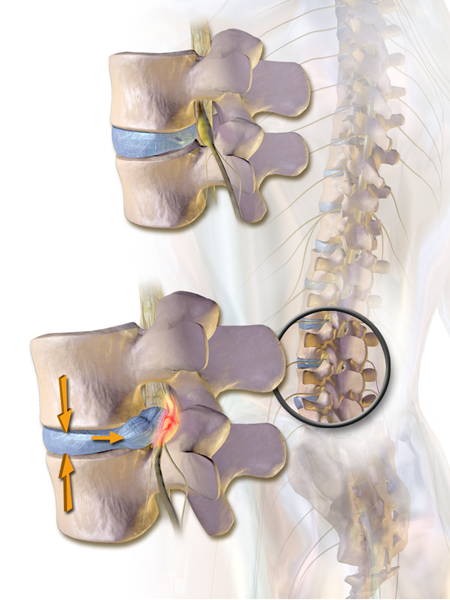

LumbarHernia

Κήλη οσφυϊκού μεσοσπονδυλίου δίσκου (κάτω), με στένωση του νευρικού τρήματος  και πίεση του εξερχόμενου νεύρου. Σύγκριση με φυσιολογικό δίσκο, τρήμα στην άνω εικόνα.